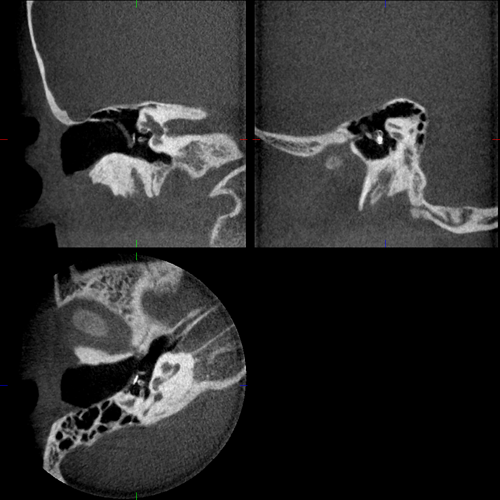

Bilder Ohr

Ambossarrosion mit Stapesprothese Stapesprothese Teflon (Causse) PORP auf Stapes PORP Titan auf Stapes PORP PORP Titan disloziiert Otosklerose Otoskleroseherd TORP Pauke nicht belüftet TORP unter Knorpelinsel disl.